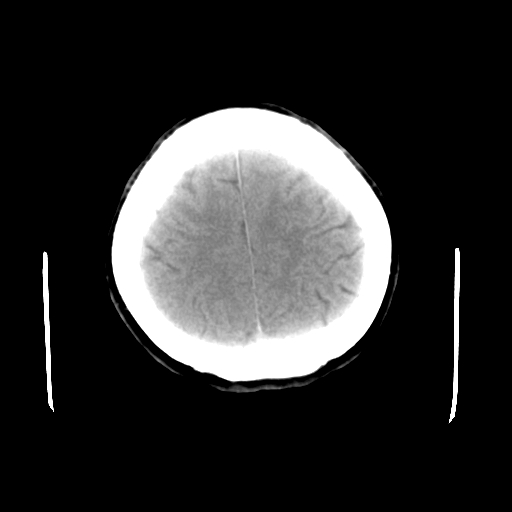

标题: CT23995:女,42岁,前额部外伤1小时,伤后头痛。

女,42岁,前额部外伤1小时,伤后头痛。

头颅ct平扫未见异常

未见明显异常!

颅脑ct平扫未见异常,必要时复查

未见明显外伤性改变。